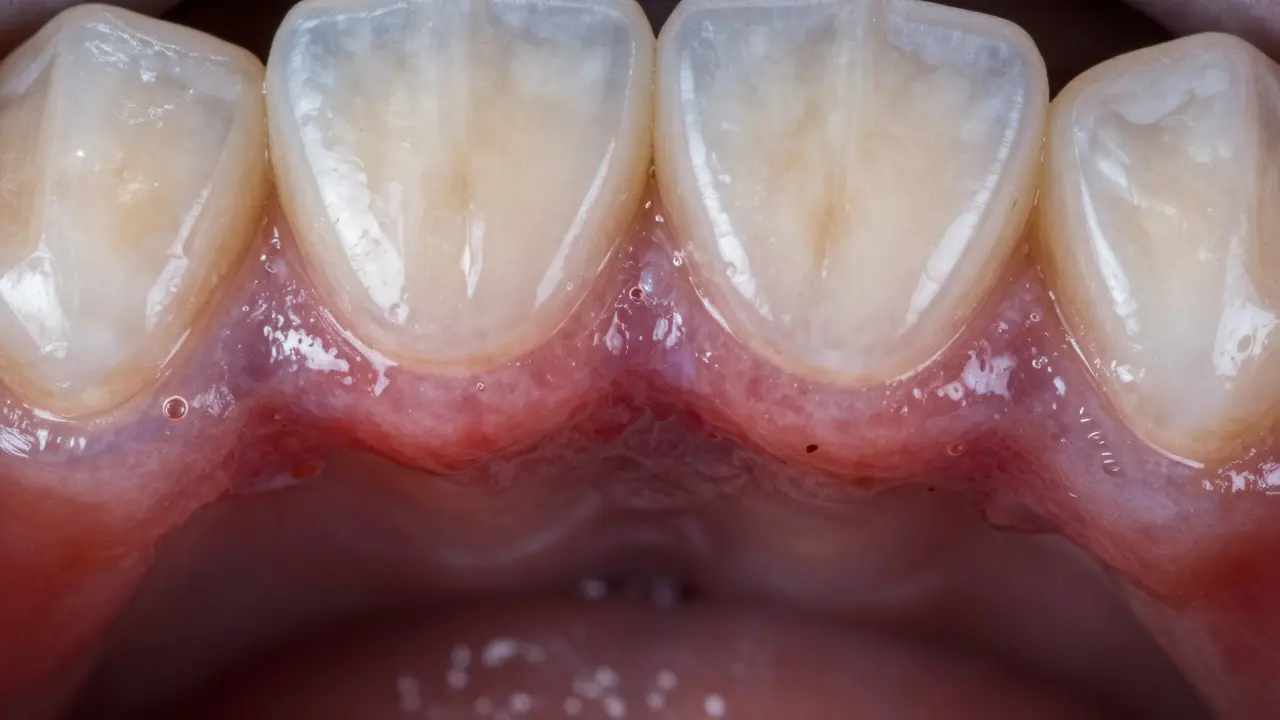

Jak zánět v puse vypadá - viditelné příznaky

Když se podíváte do zrcadla, co hledat?

• Červené nebo fialové dásně - místo zdravé růžové barvy jsou tmavší, zvětšené a lesklé

• Krvácení - i když jen lehce čistíte zuby nebo jíte tvrdší potravu

• Otěk - dásně vypadají jako „nafouknuté“, obzvláště kolem jednoho zubu

• Zápach z úst - ani dobré čištění, ani ústní voda to neodstraní

• Bolavost - při doteku, kousnutí nebo dokonce bez příčiny

• Výběh nebo hnis - malý „puklík“ na dásni, z něhož se vysouvá bílá nebo žlutá tekutina

• Zub se zvlnil - pokud je zánět dlouhodobý, kost kolem kořene se rozpadá a zub se začne hýbat

Pokud máte e-max korunku a kolem ní vidíte některý z těchto příznaků, není to „jen trochu zčervenalo“. To je signál, že infekce je pod korunkou. A e-max korunky nejsou „zázračné“ - nezastaví bakterie, pokud se dostanou pod ně.